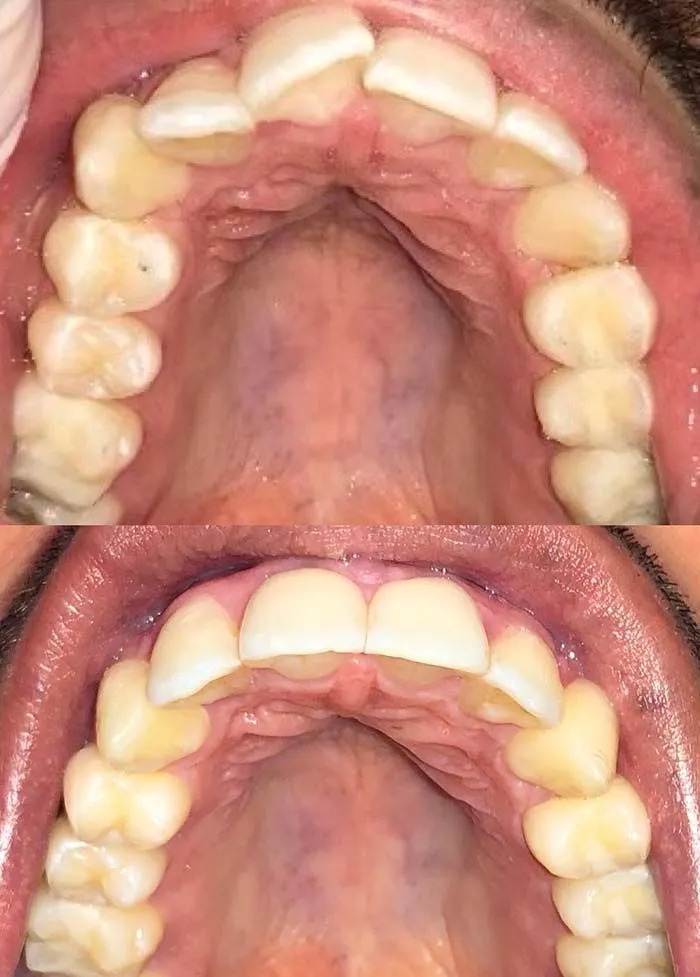

Check out our Invisalign® treatment gallery to see how this orthodontic service can straighten your teeth and improve your smile. Contact La Jolla Dental Image at 858-202-0481 today to make an appointment with our dentist, Dr. Wali Hamidy, and learn more about Invisalign clear aligners in La Jolla, California.